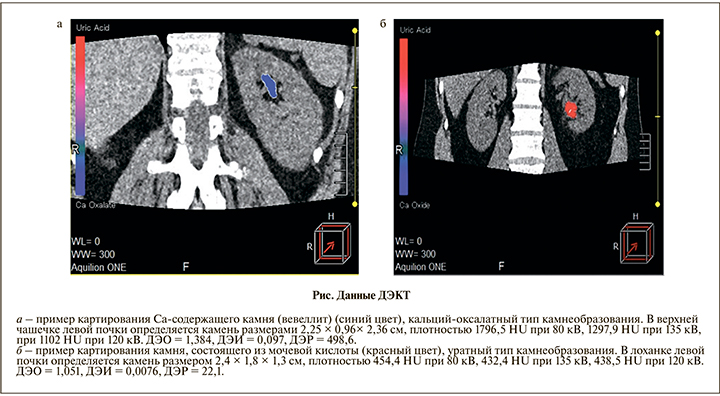

В процессе анализа изображений программа DE StoneAnalysis автоматически выполняла цветовое картирование выявленного камня, по которому можно было предварительно прогнозировать химический состав in vivo. Оксалаты кальция картировались синим цветом, камни из мочевой кислоты – красным, камни другого или смешанного состава – различными оттенками синего, голубого, фиолетового и красного цветов (см. рисунок).

Все камни по результатам ДЭКТ были распределены в четыре группы: камни из вевеллита, Ca-содержащие камни без вевеллита, камни из мочевой кислоты, струвитные камни.